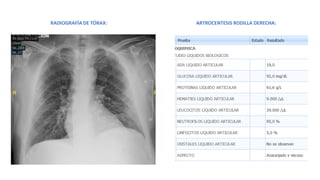

RADIOGRAFÍA DE TÓRAX: ARTROCENTESIS RODILLA DERECHA:

RADIOGRAFÍA DE TÓRAX:ARTROCENTESIS RODILLA DERECHA: